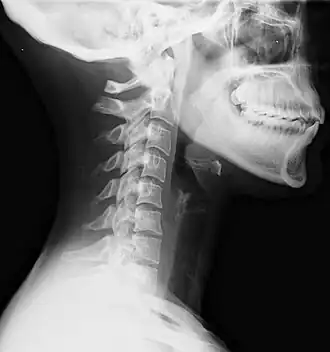

Een whiplash is een letsel aan de nek en/of rug ten gevolge van een ongeval of andere plotselinge gebeurtenis waarbij het hoofd krachtig voor en achteruit bewogen wordt. De beweging is te vergelijken met de beweging van het uiteinde van een zweep (whip in het Engels).

Het vaakst loopt men een whiplash op bij kop-staartaanrijdingen met auto's. Hierbij heeft de voorste wagen enkel kans op het letsel omwille van de mechanische beweging van de nek. Er kan hierbij een beschadiging aan zachte weefsels en structuren in de nek optreden, die aanleiding tot klachten geeft. Het grootste deel van de mensen herstelt op korte termijn.

Een CT-scan of conventionele NMR kan meestal geen uitsluitsel geven. Bij gradiënt echo opnamen (GRE-opnamen) kunnen evenwel bij een minderheid van getroffenen wel punctiforme bolvormige letsels vastgesteld worden die op bloedingen wijzen.